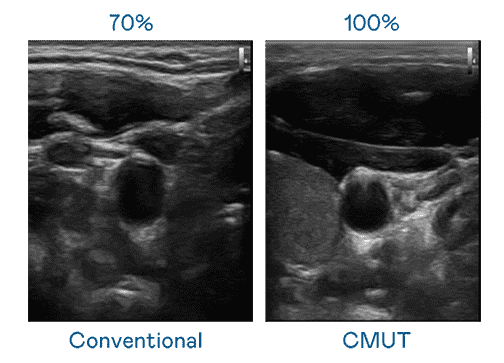

CMUT 技术是一种用电容式微机电元件来产生超音波讯号的技术。。。与传统 PZT 压电式技术相比,,,CMUT 频宽增加 30%,,,,更宽频的超音波讯号让影像解析度大幅提升,,,是实现高影像品质医疗超音波扫描、、、、促进精准医疗发展的关键技术。。。

大频宽带来超清晰影像

超音波影像的解析度高低,,,,首先取决于探头能发出的讯号频宽。。。。z6mg·人生就是博 CMUT 可提供高清晰的超音波讯号,,,,提供高频宽、、、、高灵敏度、、影像纹理细节更高的超音波影像,,,,协助医护人员缩短影像判读时间及利用精准的医疗影像进行诊断。。